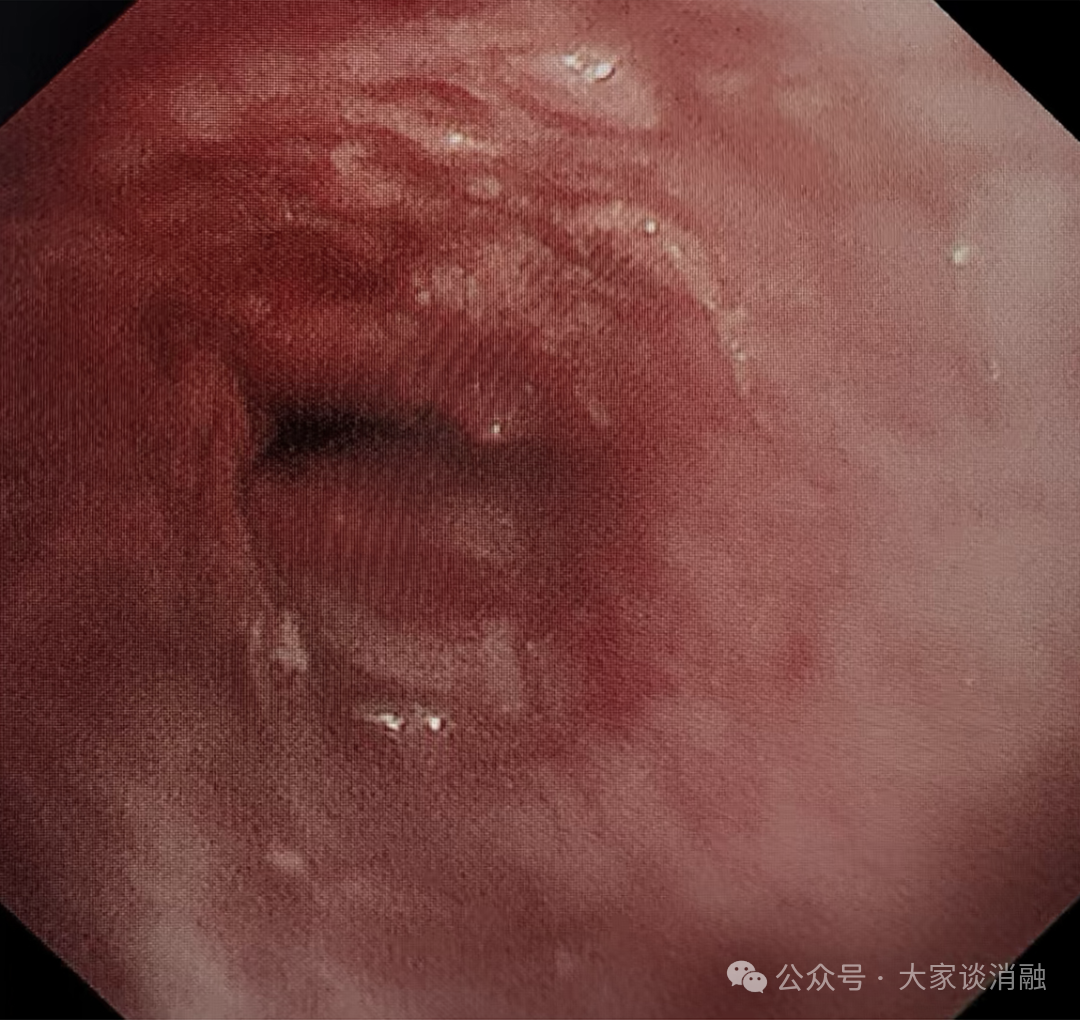

10 月 29 日,为进一步巩固疗效,患者接受术后第二次镜下消瘤治疗,冷冻冻取、钳取肿瘤组织,气道阻塞问题得到更有效解决,生活质量显著提升。目前,患者已顺利出院,回归正常生活。

下叶完全开通